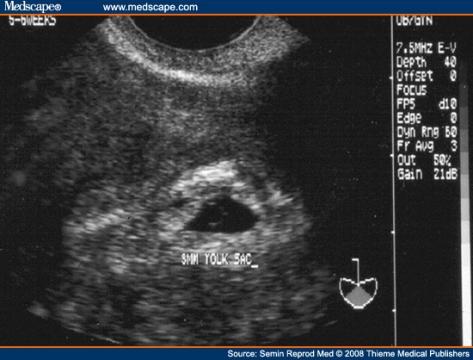

dundusa - 12.9.2011 12:19:34 Dobrý deň! Mám istý problém a rada by som sa spýtala na Váš názor. Tento mesiac 7. 9. 2011 som bola u gynekologičky na ultrazvuk a odber krvi, keďže som tehotná. Podľa výpočtu od poslednej menštruácie som bola vtedy v 5 tt + 4. Lekárka na ultrazvuku videla už embrionálne štruktúry, vyzeralo to ako bublinka (asi tak ako na priloženej fotografii - nie je to však môj ultrazvuk, len na porovnanie). Vystavila mi tehotenský preukaz, povedala mi, aby som sa objednala v októbri na integrované testy a ďalšiu návštevu, teda aj ďalší ultrazvuk mi dala až 10.10. 2011, čo budem už v 10 tt + 2! Podľa môjho názoru je to dosť neskoro, veď srdiečko vidno biť oveľa skôr, už vraj v 7 tt a ja mám prísť až tak neskoro? Čo ak srdiečko biť nebude a ja budem nosiť mŕtvy plod? Je takýto postup gynekologičky správny? Už som po jednom missed abort (zamlčanom potrate) z roku 2010 a chcem sa vyvarovať možných rizík. Ďakujem Vám za radu. S pozdravom Zuzana